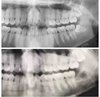

Терапия:

-Консультации

-Художественные реставрации.

-Лечение к\к вертикальная конденсация гуттаперчей.

-Лечение слизистой оболочки полости рта.

Ортопедия :

-Протезирование при частичной потере зубов

Протезирование при полной потере зубов.

-Штампованные коронки.

-металлопластмассовые коронки

-Микропротез (бабочка)

Хирургия:

-Удаление 1-корневых, 2 корневых зубов.

-Рассечение уздечки языка.